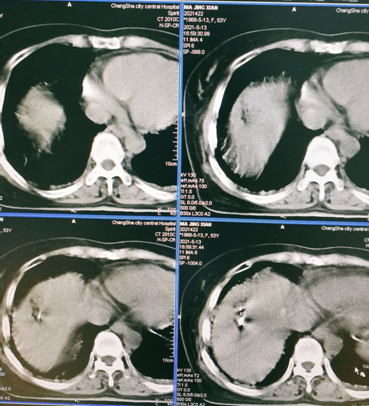

肿瘤消融术

1.肿瘤消融术技术手段的多样性-射频、微波、冷冻、激光、不可逆电穿孔等。

3.消融术在实体肿瘤治疗的应用范围广--肝、肺、肾及肾上腺、骨与软组织、乳腺、甲状腺等。